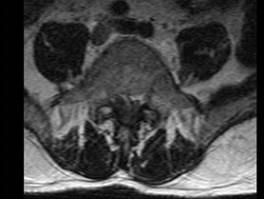

男,52岁,“坐骨神经痛”3个月余,请结合影像学检查,选出最可能的诊断 ( )A、椎间盘突出B、神经根鞘囊肿C、椎间盘炎D、硬...

相关内容:坐骨神经痛,月余,影像学,检查,选出,可能,诊断,椎间盘,神经,根鞘,囊肿